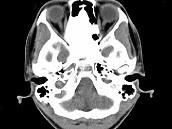

问题 女,17岁,鼻阻塞、头痛两年.如图所示符合筛骨病变最可能的诊断是()

选项 A.成骨肉瘤骨 B.纤维异常增殖症 C.软骨瘤 D.骨瘤 E.骨化性纤维瘤

答案 E